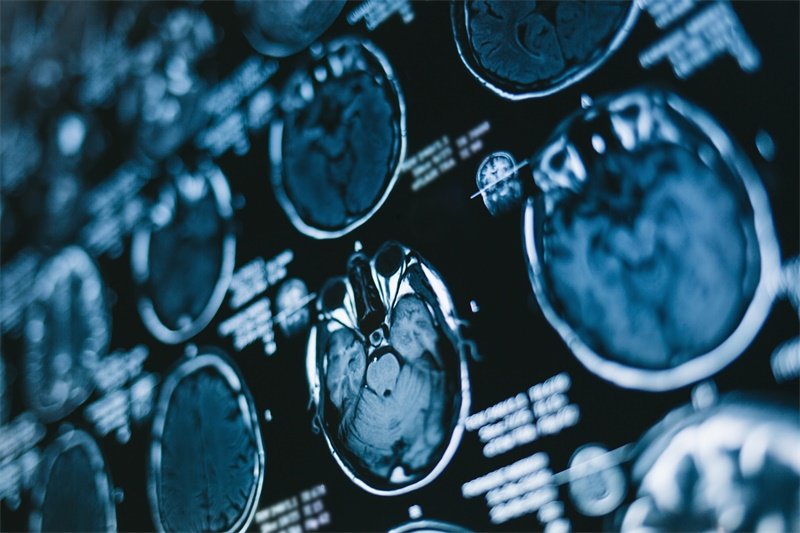

在我们深入探讨之前,首先需要了解一些基础知识。“左侧侧脑室后角”是指大脑中的一个解剖结构,它位于侧脑室的后方。侧脑室的后角是大脑内的一部分,人脑中有两个侧脑室(左侧和右侧)。而“旁囊性占位”则意味着在该区域附近存在囊肿或占位性病变,这通常显示为CT或MRI成像上的液体填充囊泡。

影像学检查是诊断脑部病变的重要手段。CT扫描和MRI都是可以清晰显示脑部结构及任何异常占位的有效方式。通过这些影像检查,医生能够判断囊肿的大小、位置以及周围脑组织的状态。